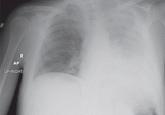

ArticlePleural effusion from a candy wrapperAuthor:Smyrna Abou Antoun, MDPublish date: November 1, 2009A 60-year-old man presents with worsening shortness of breath and productive cough. Flexible bronchoscopy reveals the surprising cause.Read More